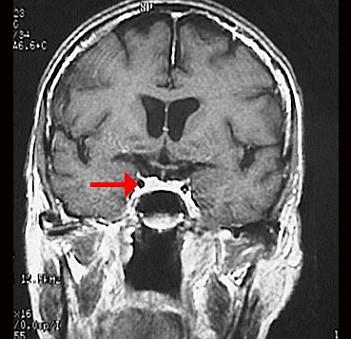

问题 如图箭头所示为大脑哪根动脉 ( )

选项 A、基底动脉 B、大脑后动脉 C、颈总动脉 D、大脑中动脉 E、颈内动脉 一、单项选择题

答案 E